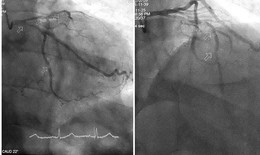

Người đàn ông sốc tim, nhồi máu cơ tim do lạm dụng chích lể tại nhà

Y tế - 29/08/2025 11:44SKĐS - Một người đàn ông thường xuyên đau tức ngực, khó thở, mệt mỏi nhưng không đi khám mà chỉ chích lể tại nhà dẫn đến sốc tim, nhồi máu cơ tim cấp do tắc động mạch vành.